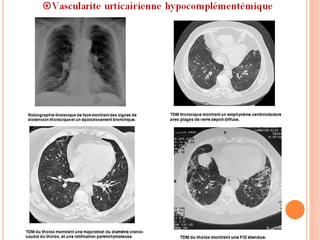

Atteinte pulmonaire:

 26% à 65%.

 Plus fréquente chez les fumeurs.

 Symptômes principaux : dyspnée et toux ++.

 Plus rarement : douleur thoracique, expectoration,

hémoptysie, HIA et épanchement pleural.

 Pneumopathie obstructive ++ .

 TVO dans près de 50 % des cas.

 Un emphysème pulmonaire dans moins de 50 % des cas.

La consommation de tabac semble

corrélée à la sévérité des lésions.